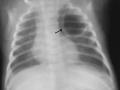

Intubação seletiva em recém-nascido

Dez de 2015.

16.089